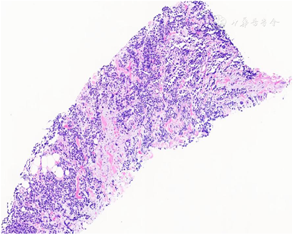

病理检查:送检双侧前列腺穿刺组织8条(左1至左4、右1至右4各一条),长度0.2cm~1.5cm,直径均为0.1cm。镜下观察:其中左2至左4可见良性前列腺腺体,其余5条均为纤维肌性脂肪组织,8条组织内均可见多灶呈小巢、片状以及腺泡样结构的幼稚深染短梭形或卵圆形肿瘤细胞增生、浸润(图2,图3),瘤细胞胞质稀少,核不规则,染色质深,核分裂象和凋亡小体多见,偶见胞质强嗜酸性的横纹肌母细胞样细胞,间质可见带状胶原纤维沉积和局灶的黏液变性(图4,图5)。免疫组织化学染色:肿瘤细胞弥漫核表达MyoD1(图6),大部分表达Myogenin(图7),部分表达结蛋白,弥漫表达CD56,Olig-2局灶表达,约5%(图8),ALK个别细胞表达,弥漫胞质表达WT1和波形蛋白,S-100蛋白阴性,Ki-67增殖指数约70%。荧光原位杂交(FISH)分别检测PAX3和FOXO1基因分离:PAX3和FOXO1基因重排均阳性(图9,图10)。